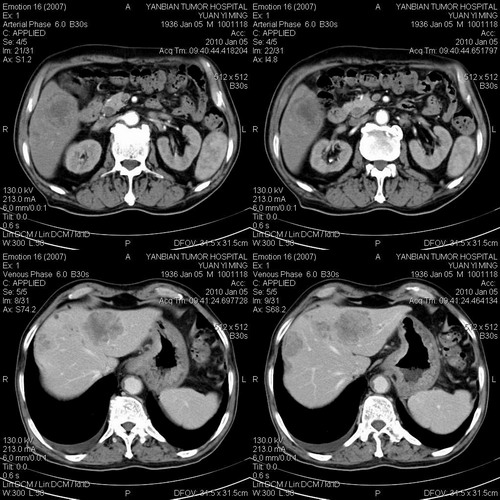

标题: CT24024:男,74岁。体检超声发现肝内多发占位性病变四天。 [打印本页]

标题: CT24024:男,74岁。体检超声发现肝内多发占位性病变四天。

1)考虑肝脏恶性肿瘤(转移瘤?)。2)肝外胆管轻度扩张。3)左肾小囊肿。

考虑多发结节性肝癌。

考虑肝脏恶性肿瘤(转移瘤?)。2)肝外胆管轻度扩张。3)左肾小囊肿。